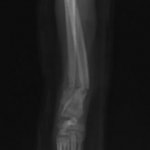

症例3:キルシュナーワイヤーのピンニングによる整復

ペルシャ猫 11ヶ月齢 雄

他院にて左大腿骨遠位の成長板骨折(salter-harrisⅠ型)が認められており、治療相談を目的として来院。当院にて、キルシュナーワイヤーを用いたピンニングにより骨折部位の整復を行いました。術後の経過は良好で、現在も経過観察中です。

術前レントゲン

術後レントゲン